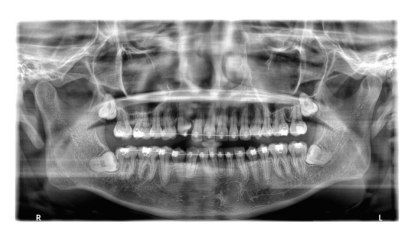

BEFORE

治療経過

AFTER